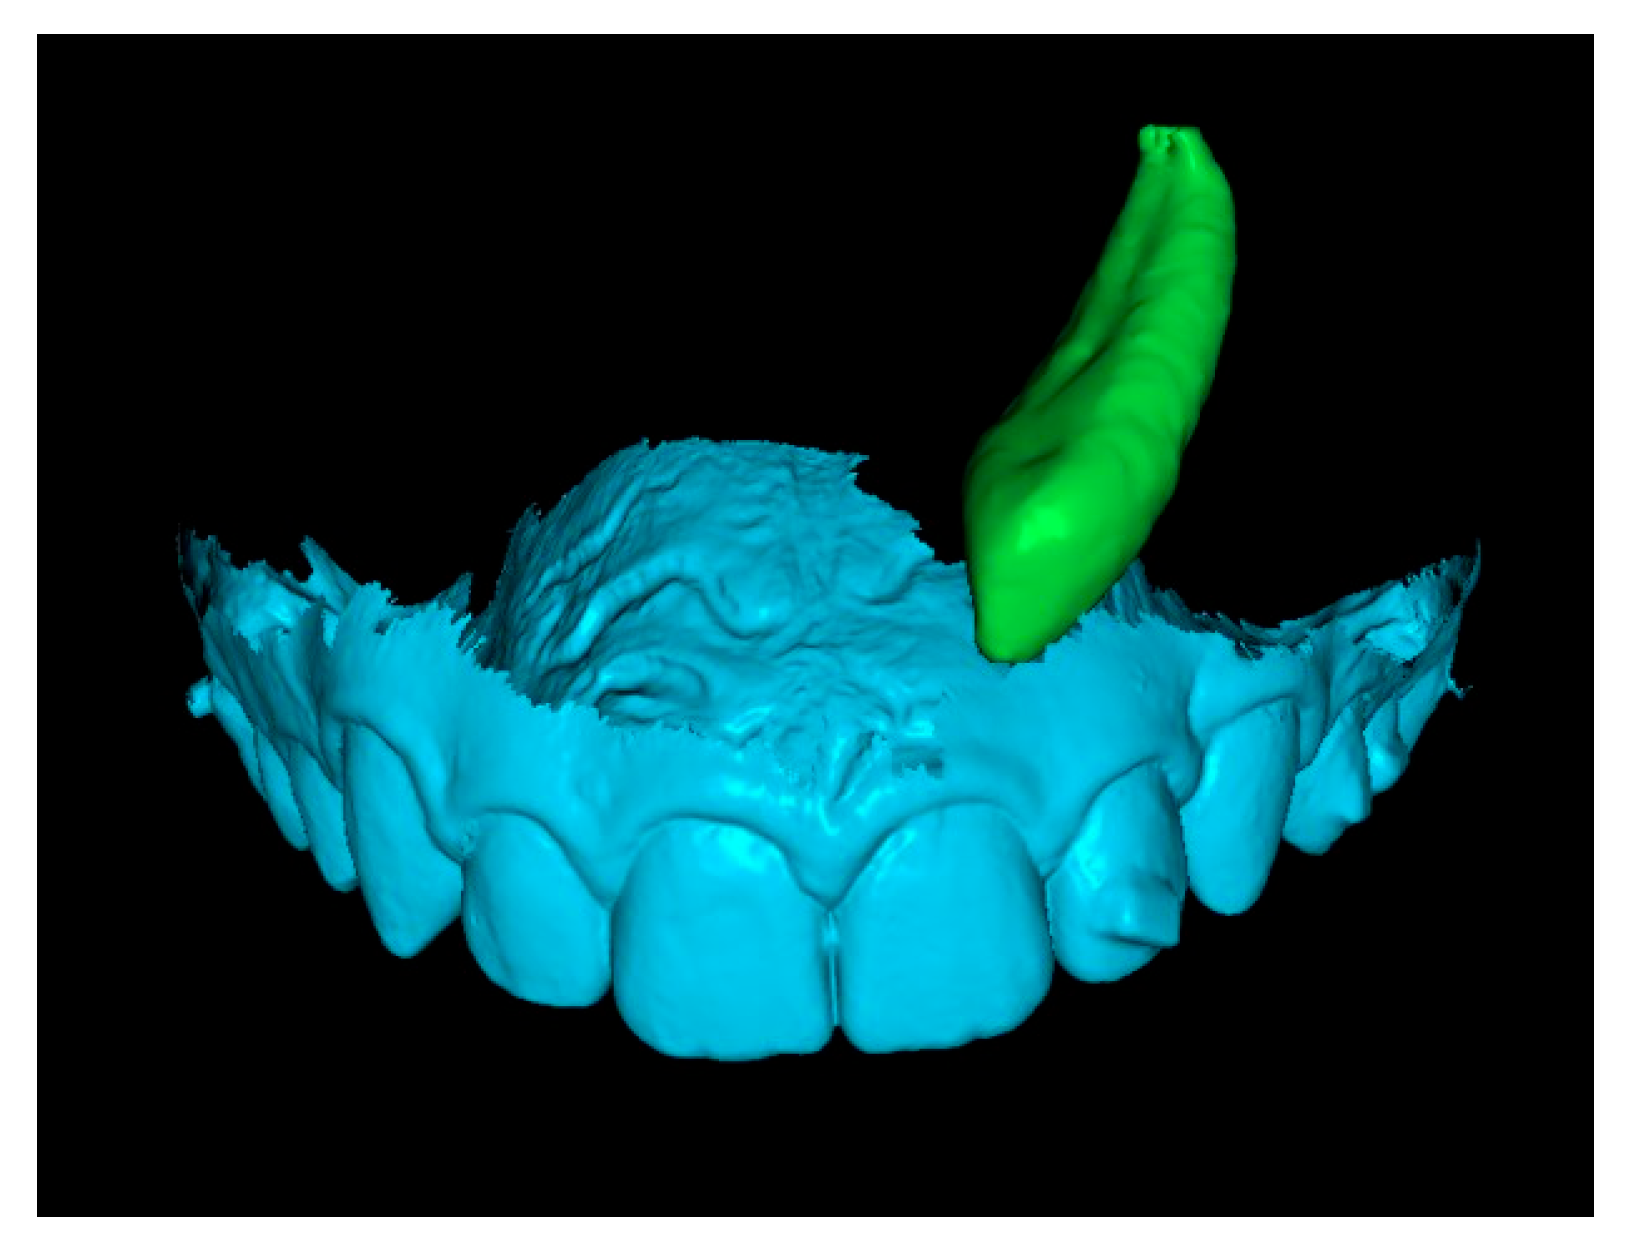

Third step: Overlay of Initial STL with IC and Final STL.

The initial STL combined with the IC was superimposed onto the final STL by marking stable reference points on the palatal rugae (Figure 6). This process resulted in a final STL model that includes the initial position of the IC (Figure 7).

Figure 6.

Superimposition of initial and final STL models using palatal rugae.

Figure 7.

Final STL including the initial 3D position of the IC.

Fourth step: Overlap the Initial Canine with the Crown of the Canine in the Final STL.

Since the final STL does not include tooth roots, only the crowns of the initial and final canines were overlapped. This alignment positioned the canine in its final position after traction. In some cases, after overlapping, the apex of the canine was not visible (Figure 8). When this occurred, a small cut was made to enable visualization of the apex.

Figure 8.

Overlay of canine in initial and final positions.